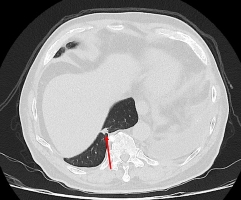

75歲吳先生因肝臟細胞癌在仁愛長庚合作聯盟醫院(大里仁愛醫院)接受治療,期間發現右下肺有一顆約1.2公分新發現的腫瘤,因疑似肺癌故轉介到胸腔及心臟血管外科廖啟耀主任門診,經醫療團隊和家屬討論後決定做手術切除該腫瘤。由於病人過去有車禍導致橫隔膜受傷的病史,所以讓手術預期難度相對提高,經採用達文西機器人手術系統執行肺節切除手術,並且順利地於術後第三天出院返家休養。

廖啟耀主任指出,仁愛與長庚醫療體系聯盟醫院近年來積極引進達文西機器人手術系統,並成立微創暨達文西手術中心,致力推動高品質、低侵襲性的手術照護。手術中病人的橫隔膜如果符合預期和肺臟沾黏,因此手術空間也較為狹小,達文西機器人手術可提供穩定的操作及清晰的手術視野,這對於外科醫師在分沾黏上是如虎添翼。達文西手術在這方面優勢更顯得突出,透過穩定且精細的操作,團隊將吳先生的橫隔膜與肺臟分離,並完成之後的肺節切除手術。

雖然因為外傷病史使手術困難度上升,廖啟耀主任的團隊藉由達文西機器人手臂幫助下成功完成手術,過往使用傳統開胸手術或胸腔鏡手術於類似的病人,常因為分沾黏導致肺破損所以需要較長的恢復時間,但是在進行達文西手術的過程中,不只術中沒有發生因為分沾黏常見的出血、肺破損等問題,吳先生在術後第二天便可拔除胸腔引流管,恢復順利。